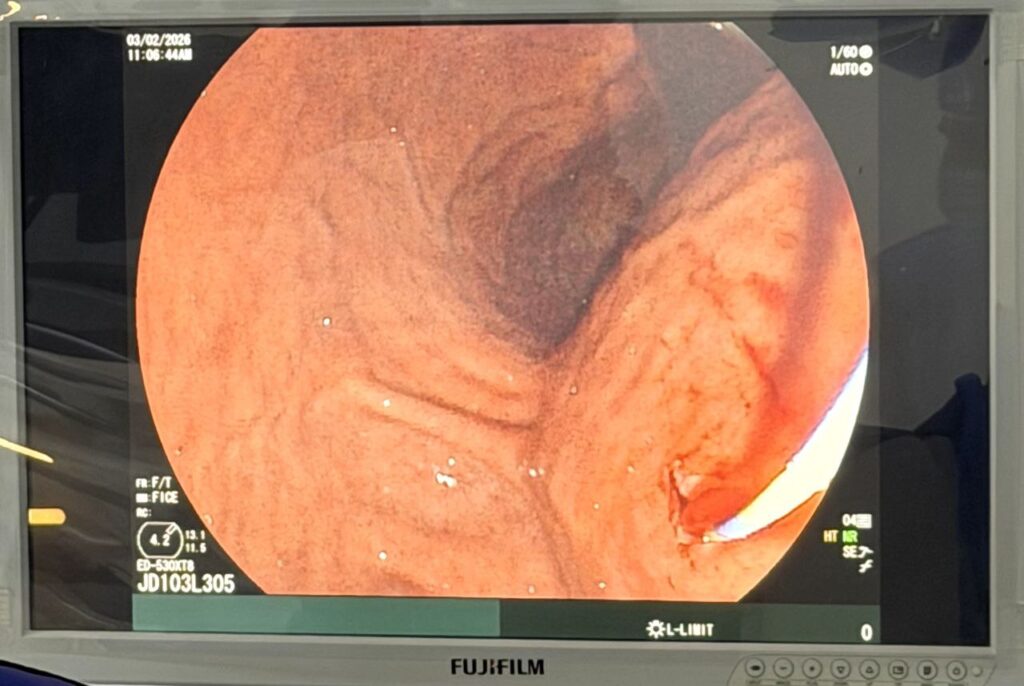

Ба табибони маркази мазкур имкон даст дод, ки бори аввал дар Тоҷикистон ба бемори 22-солаи дорои кистаи қисми бадани ғадуди зери меъда бо усули эндоскопӣ, яъне бе буриш тавассути даҳон систогастростомияи эндоскопӣ гузаронанд.

Тавре Мусоев Сорбон Шералиевич иброз дошт, дар рафти ташхис дар бемор кистаи бадани ғадуди зери меъда бо андозаи 17×9 см ошкор карда шуд, ки ин ҳолат девори қафои меъдаи беморро фишор додаву бо пайдо гаштани дард ҳолати дилбеҳазурӣ ва қайдкуниро ба вуҷуд оварда, инчунин гузариши ғизоро ба рудаи дувоздаҳгузашта душвор мекард.

“Барои бартараф намудани мушкилоти мавҷуда ба бемор пунксия ва катетеризатсияи киста тавассути девори қафои меъда таҳти назорати эндоскоп гузаронида шуда, бо истифодаи систографияи эндоскопикӣ, яъне дохил намудани ранг (контраст) ба дохили киста анҷом дода шуд. Ковокии кистаи бемор, ки бо андозаи 17×9 см муайян шуда буд, дар он стенти пластикии навъи “pigtail” бо дарозии 11 см ва диаметри 10 Fr гузошта шуд, ки дар нитҷа аз дохили стент моеъи шаффоф бо фишор ба меъда хориҷ шуд”,- гуфт номбурда.

Ба зикри ҳамсуҳбати мо, систогастростомия бо усули эндоскопии зери назорати ултрасадо ва рентген иҷро карда шуда, пас аз 24 соати амалиёти ҷарроҳӣ ташхиси назоратии ултрасадои узвҳои шикам коҳиши андозаи кистаро дар бемор то 4 см нишон дод ва бемор ба хона рухсат дода шуд.